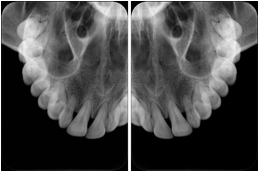

OO.1.2 Ophthalmology

1. A patient in rural Canada visits a general ophthalmologist and is found to have diabetic macular edema. The general ophthalmologist would like to discuss the case with a retina specialist before performing laser surgery. A fluorescein angiogram is done with multiple retinal images taken in a timed series after an intravenous injection. The images along with a Structured Display are shared via a Health Information Exchange with a retina specialist in Calgary, who opens them using his Ophthalmology EMR software and consults via phone with the general ophthalmologist. Both physicians view the images in the same layout so the retina specialist can provide accurate guidance for treating the patient.

2. A patient in rural Iowa visits his primary care physician for management of diabetes. Three non-mydriatic (patient's eyes are not dilated) photographs are taken of the back of each eye, and forwarded electronically along with a Structured Display to an ophthalmologist in Iowa City. The ophthalmologist reads the photos in an agreed upon layout so there is no mistake about what portion of which eye is being viewed. The ophthalmologist is able to tell the primary care physician that his patient does not need to come to Iowa City for face to face ophthalmologic care, but that there is a particular view of the left eye that should be photographed again in 6 months.

Ophthalmic Retinal Study Structured Display

Figure OO-3. Ophthalmic Retinal Study Structured Display